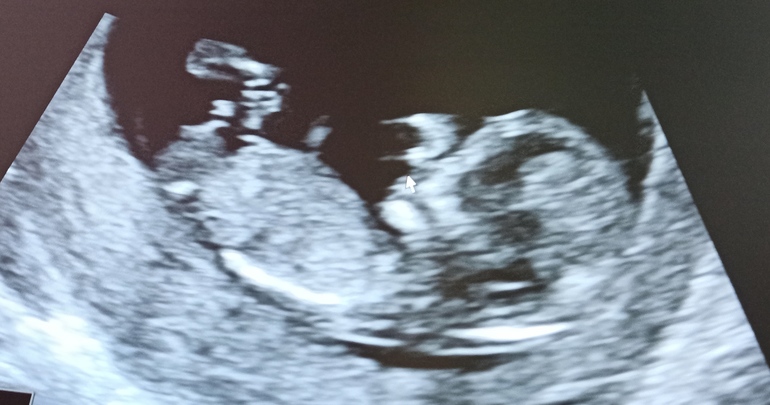

Как думаете, мальчик или девочка?

Пол малышаУзист сказала, что пока не хочет вводить в заблуждение, непонятно))) а вы как думаете?